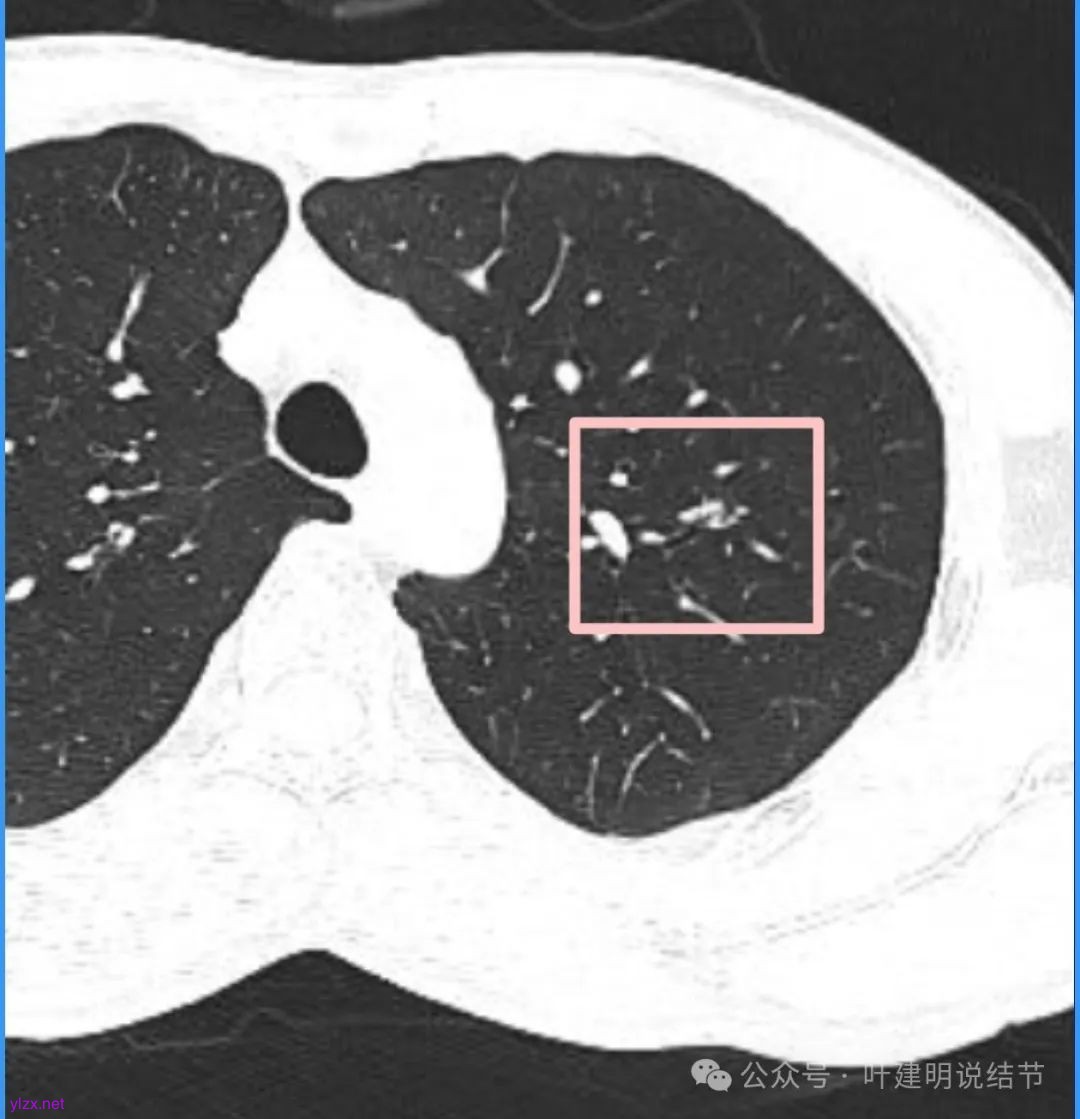

左肺上叶这个病灶总体上来讲2025年3月的与2024年11月份相比没有显著进展。我们逐层从细节上去分析,会发现:1、病灶开始出现的层面就有临近的支气管扭曲变形,这些人用肿瘤导致的牵拉不能解释,反而用细支气管扩张伴慢性炎容易解释;2、病灶内部仍然多个层面都有见到扩张的细支气管,可是如果是肿瘤,与导致细支气管扩张相应的病灶本身的收缩力或者边缘毛刺又不明显;3、病灶边缘基本上都比较光滑平直,没有像外周浸润性生长的枫叶或者毛刺;4、虽然有血管贴边或者进入,但是说不上显著的血管异常增粗;5、整体来讲病灶实性成分密度过高,随访对比进展不明显,用结节是恶性不太能够解释相应的影像表现,所以我倾向于考虑是细支气管扩张伴有周围慢性炎或者肉芽肿性炎。至少从风险高低的角度来看,几个月的间隔没有明显进展的情况下加上位置又不好,如果手术需要切除范围比较多,所以应该在随访观察比较稳妥,可以考虑半年复查对比。意见供参考!